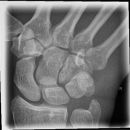

Handgelenk seitlich

Beurteilungskriterien

- Neigung der distalen Radiusgelenkfläche in der Sagittalebene: 10 – 15°

- Kontinuierliche Verlängerungsachse durch Radius, Lunatum, Capitatum und Os metacarpale III. Kontinuität von Handrücken und Unterarmrückfläche (Luxation, nicht-exakte Einstellung? -> Proc.styloideus ulnae im hinteren Radiusdrittel?)

- Scapholunärer Winkel 30 – 60°

- Verstreichen und Ventralverlagerung der volaren Fettstreifen vor dem M.flexor digitorum profundus und M.pronator quadratus

- Grundsätzlich gilt: unklare Verhältnisse -> CT-Indikation

Beispiele

Smith-Fraktur (2) volare Fragmentabkippung

Colles- Fraktur (2) dorsale Fragmentabkippung

Chauffeur-Fraktur (2) radialer Keilbruch

Barton-Fraktur (2) intraartikulär, dorsales Kantenfragment

Reversed Barton-Fraktur (2) intraartikulär, volares Kantenfragment